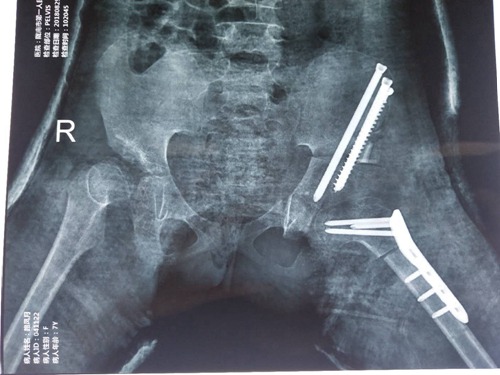

术后复查X线图

手术在黄鲁豫教授的指导下进行,手术过程顺利,术后患儿病情平稳,复查X线可见内固定稳定,髋臼包容良好。